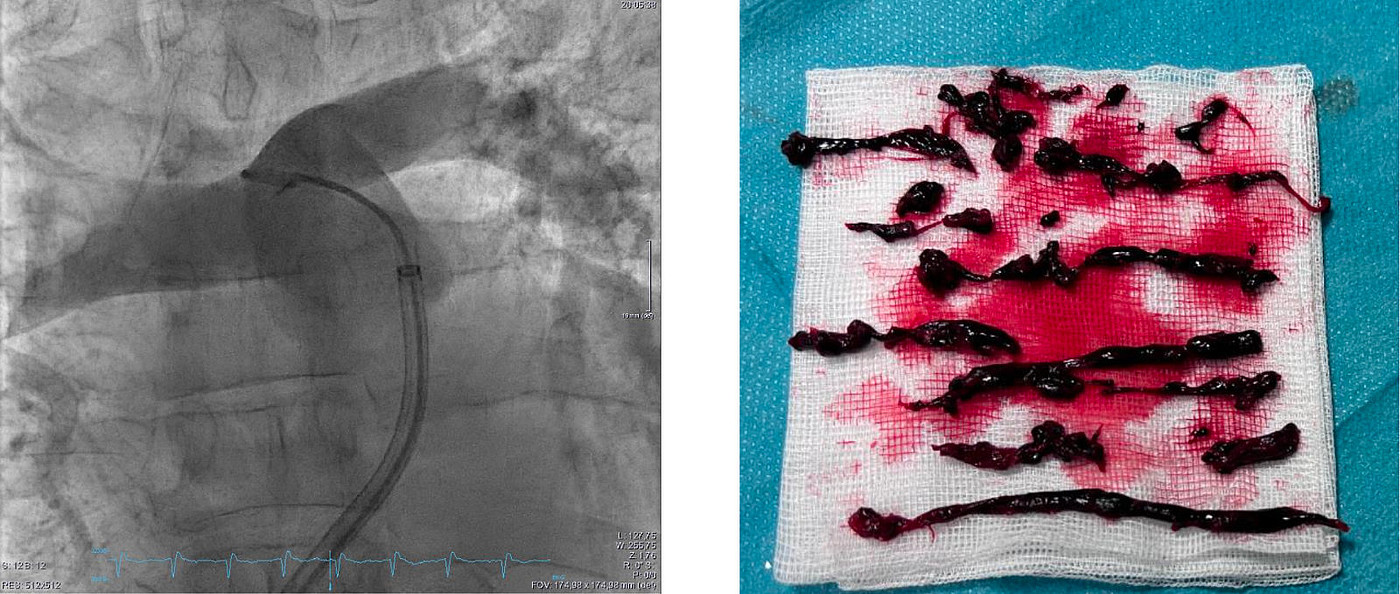

An der UMM wurde der erste Patient in Deutschland in die STRIKE-PE-Studie aufgenommen – ein wichtiger Schritt für neue Therapien bei Lungenembolie.

In der Studie werden kathetergestützte Therapieverfahren bei Patient:innen mit intermediär-hochrisiko Lungenembolie untersucht. Diese minimalinvasiven Ansätze sollen die Versorgung verbessern und Komplikationen reduzieren – insbesondere bei Menschen mit erhöhtem Risiko. Mit dem erfolgreichen Einschluss des ersten Patienten in Deutschland stärkt die UMM ihre Rolle als Studienstandort und erweitert gleichzeitig das Behandlungsspektrum im Bereich der interventionellen Lungenembolietherapie.